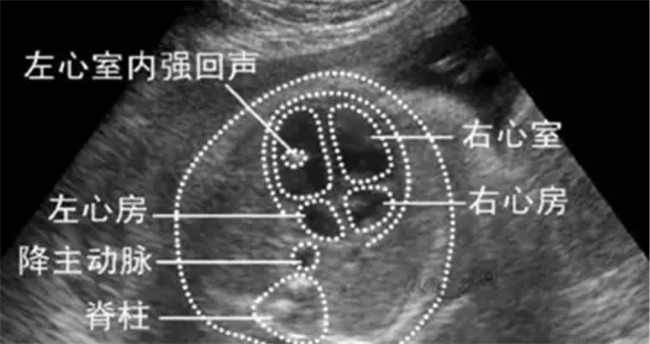

胎儿心脏彩超是一种非侵入性的检测方法,能够动态显示胎儿心脏内部的结构、心脏的跳动以及血液流动情况。通过像摄像机一样的心脏探头,医生可以在屏幕上清晰看到心脏的各个部位,从而检查其形态是否正常,心功能是否正常运作。这项检查对于早期发现先天性心脏病尤为重要,因为先天性心脏病是一种常见的先天性缺陷,严重者可能会影响胎儿的健康和生存。

先天性心脏病的发生率虽然较低,但一旦出现,其治疗难度大,对家庭和社会都会造成不小的负担。通过胎儿心脏彩超,可以高度敏感地筛查出心脏发育异常,尤其是那些预后较差的严重畸形,如心脏外翻、单心室、单腔心等。研究显示,胎儿心脏彩超在诊断胎儿心脏畸形方面的敏感度高达95%,准确性超过85%以上。